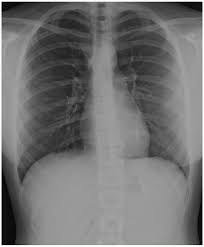

2. Radiology Residency Essentials: Diaphragm Imaging Explained By Dr. Aisha Khan

This session is a goldmine for residents struggling with diaphragm imaging. It breaks down complex anatomy and physiology, and connects it to real-world pathologies.

Key learning points:

• Basic anatomy and embryology of the diaphragm

• Important physiological roles (beyond respiration!)

• Common pathologies like diaphragmatic eventration, paralysis & congenital hernias

• Key imaging modalities: X-ray, Ultrasound (B-mode & M-mode), CT & MRI

• Clinical relevance of phrenic nerve involvement and more!

Click Here to Watch